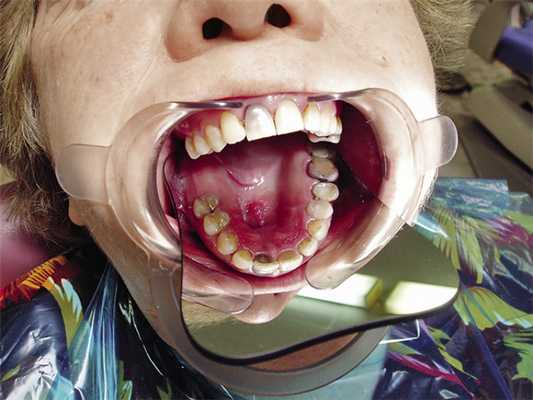

Анамнез: 4 года назад была проведена первая операция по поводу хондромы верхней челюсти, месяц назад был поставлен диагноз: рецидив хондромы верхней челюсти. В полости рта в передней трети твердого неба отмечается безболезненный узел с неровной поверхностью размером 8х15 мм и сквозной дефект, сообщающийся с гайморовой пазухой размером 7х10 мм (рис. 2).

Рис. 2. Клиническая картина верхней челюсти (до операции).

Все это время пациентка пользуется частичным пластиночным протезом-обтуратором с проволочными гнутыми кламмерами (рис. 3).

Традиционно считалось, что кламмеры не должны препятствовать осадке протеза, увеличивающей плотность прилегания протеза к небу и тем самым герметичность закрытия дефекта. Поэтому кламмеры с окклюзионными накладками применять в таких случаях не рекомендовалось. Отчасти это оправданно, но, с другой стороны, имеет место повышенное (нефизиологическое) давление пластиночного протеза на подлежащие ткани. На рис. 2 на небе отчетливо видна проекция дистальной границы протеза с явными изменениями слизистой оболочки полости рта в этой области. Поэтому мы посчитали целесообразным применение цельнолитых опорноудерживающих кламмеров системы Нея. Учитывая, что в процессе пользования протезом возможно изменение размеров дефекта и бывает необходима уточняющая перебазировка базиса, небо выполнено в виде сетки, которая будет находиться внутри пластмассы (рис. 7, 8).